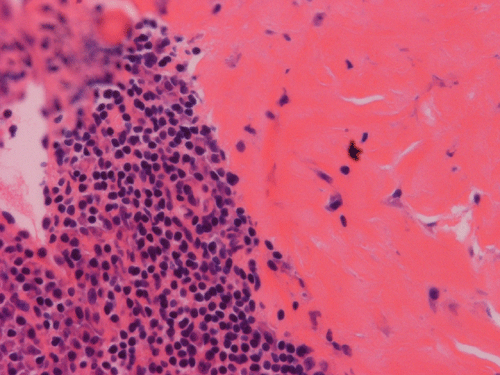

Pathology of the Case: Macroscopically, the nodules are well circumscribed, irregular, and stone hard. The cut surface is solid, gray-white, and free of necrosis. An intraoperative frozen section was performed to rule out metastatic carcinoma, Hodgkin's and non-Hodgkin's lymphoma, and sarcoma. Histologically, the material submitted for frozen section demonstrated hyalinized, hypocellular fibrous tissue with large, calcified nodules (Panel A and B). The section submitted for frozen sections was similar. The bulk of the specimen is composed of hypocellular, hyalinized collagenous tissue with occasional small irregular islands of chronic inflammatory cells (Panel C and D). The nuclei does not display significant nuclear atypia (Panel E). Many large psammoma bodies (Panel F and G)  are present and they are not associated with inflammatory cells. There are also extensive areas with no evidence of either calcifying nodules or inflammatory cells (Panel H). A segment of colon was also resected and the pathology is consistent with Crohn's disease.

Calcifying fibrous tumors are often well circumscribed, firm masses most commonly ranging in size from 1 to 4 cm in greatest dimension. However, the lesions can reach up to 15 cm.  Microscopically, the tumor is a well circumscribed mass showing diffuse hyalinization and benign appearing spindle cells intermixed with a prominent chronic inflammatory infiltrate. The inflammatory component is composed mainly of lymphocytes, eosinophils, and mast cells.  There is usually no hypercellular areas, significant atypia, or mitotic activity. Necrosis and hemorrhage are not seen. This lesion is not infiltrative. As the name implies, a hallmark of the lesion is the presence of calcifications, which may be psammomatous or dystrophic and are sometimes associated with foreign body type giant cell reaction.  It is believed these lesions are reactive because there is no documented evidence of cytogenetic or molecular disruptions that may suggest clonality 8